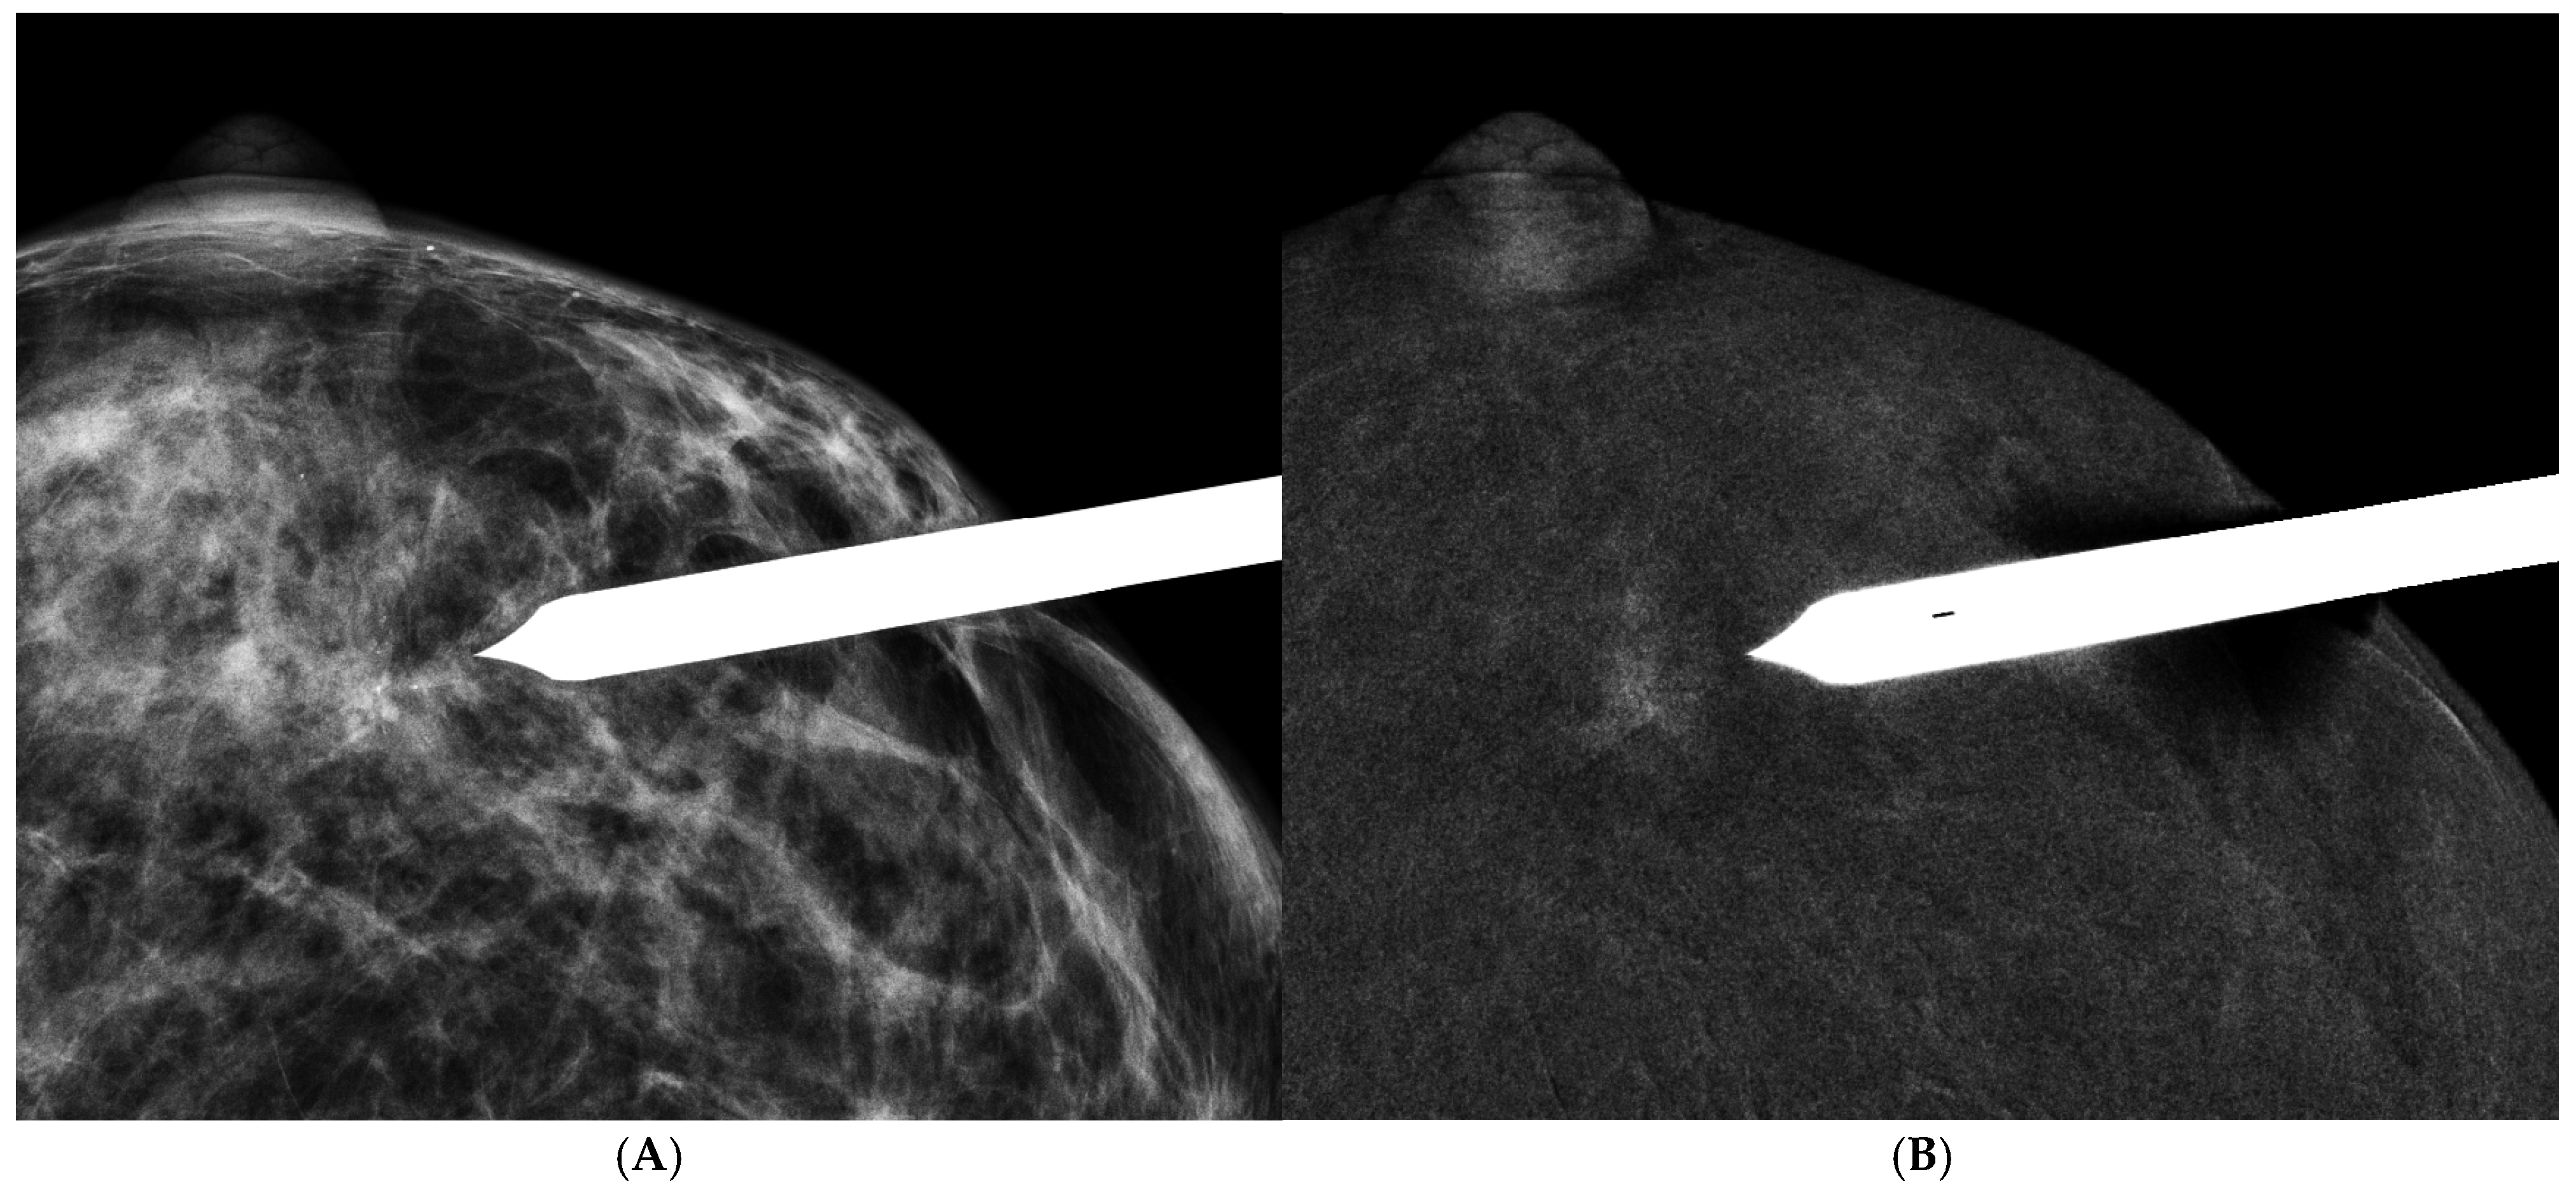

- GE Healthcare Receives FDA Clearance of the Industry’s First Contrast-Enhanced Mammography Solution for Biopsy. Available online: https://www.ge.com/news/press-releases/ge (accessed on 8 October 2020).

- Alcantara, R.; Posso, M.; Pitarch, M.; Arenas, N.; Ejarque, B.; Iotti, V.; Besutti, G. Contrast-enhanced mammography-guided biopsy: Technical feasibility and first outcomes. Eur. Radiol. 2023, 33, 417–428. [Google Scholar] [CrossRef] [PubMed]

- Kornecki, A.; Bhaduri, M.; Khan, N.; Nachum, I.B.; Muscedere, G.; Shmuilovich, O.; Lynn, K.; Nano, E.; Blyth, L. Contrast-Enhanced Mammography-Guided Breast Biopsy: Single-Center Experience. AJR Am. J. Roentgenol. 2023, 220, 826–827. [Google Scholar] [CrossRef]

- Tang, Y.C.; Cheung, Y.C. Contrast-enhanced mammography-guided biopsy: Technique and initial outcomes. Quant. Imaging Med. Surg. 2023, 13, 5349–5354. [Google Scholar] [CrossRef]

- James, J. Contrast-enhanced spectral mammography (CESM)-guided breast biopsy as an alternative to MRI-guided biopsy. Br. J. Radiol. 2022, 95, 20211287. [Google Scholar] [CrossRef] [PubMed]

- Cheung, Y.C.; Kuo, W.L.; Lee, L.Y.; Tang, Y.C. A case report of breast cancer in silicone-injected breasts diagnosed by an emerging technique of contrast-enhanced mammography-guided biopsy. Front. Oncol. 2022, 12, 884576. [Google Scholar] [CrossRef] [PubMed]